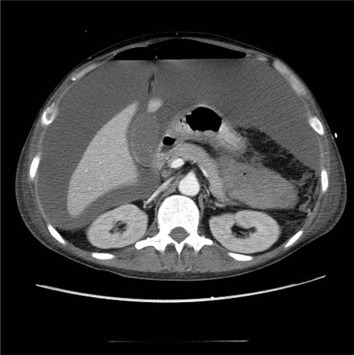

However, the patient continued to suffer from aggravating bloody diarrhea and abdominal fullness from July 2013. No body weight loss was noted during this period. Sigmoidoscopy revealed severe inflammation of the rectal mucosa and deep skip ulcerations with spontaneous bleeding (Fig. 2). He was referred to the emergency department of our hospital. On physical examination, pale mucosa and periumbilical abdominal tenderness were noted. The blood test results showed hemoglobin: 6.1 g/dL, WBC: 7.06 k/μL, Seg: 76%, Band: 16%, and platelet counts: 283 k/μL. The biochemistry test showed Alb: 3.1 g/dL, BUN: 25.3 mg/dl, Cre: 1.1 mg/dL, and CRP: 14.05 mg/dL. A stool sample showed 4+ occult blood and two to five pus cells/HPF. No protozoa or parasite ova were found in the stool. Empirical antibiotics with the third generation of cephalosporin, intravenous-form steroid [methylprednisolone 20 mg/day], and mesalamine were prescribed. However, bloody stool (>5 times/day), hypotension, and anuria developed. Stool tests, including protozoa, parasite ova, and bacterial cultures, all appeared negative. As hypoxemia progressed, intubation was performed. Hemodialysis was arranged, but the routine screening revealed anti-HIV antibody positive and western blot analysis confirmed the positive status of an HIV infection. The HIV viral load was 141,000 cp/mL. His hemogram showed WBC 14.32 k/μL, seg: 89.1%, Band: 8.9%, Meta: 1%, Lymph: 0%. The CD4 count was zero. A sudden onset of severe abdominal distension with peritoneal signs occurred, and a CT scan showed air in the rectum wall (Fig. 3), massive ascites, and free air in the abdomen (Fig. 4).

Figure 3. Abdominal CT scan image revealing the distended rectum with surrounding air pocket. |